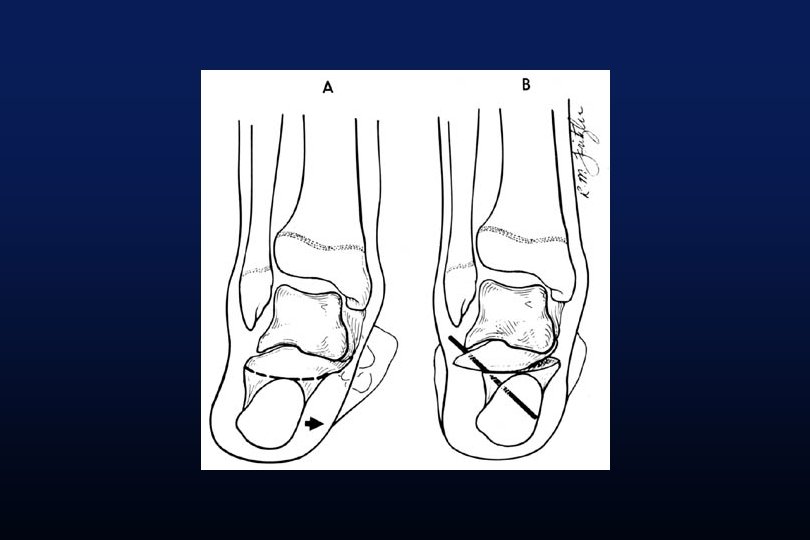

TRANSLATION MEDIALE ABAISSEMENT DE LA GROSSE TUBEROSITE DU CALCANEUS

Evans